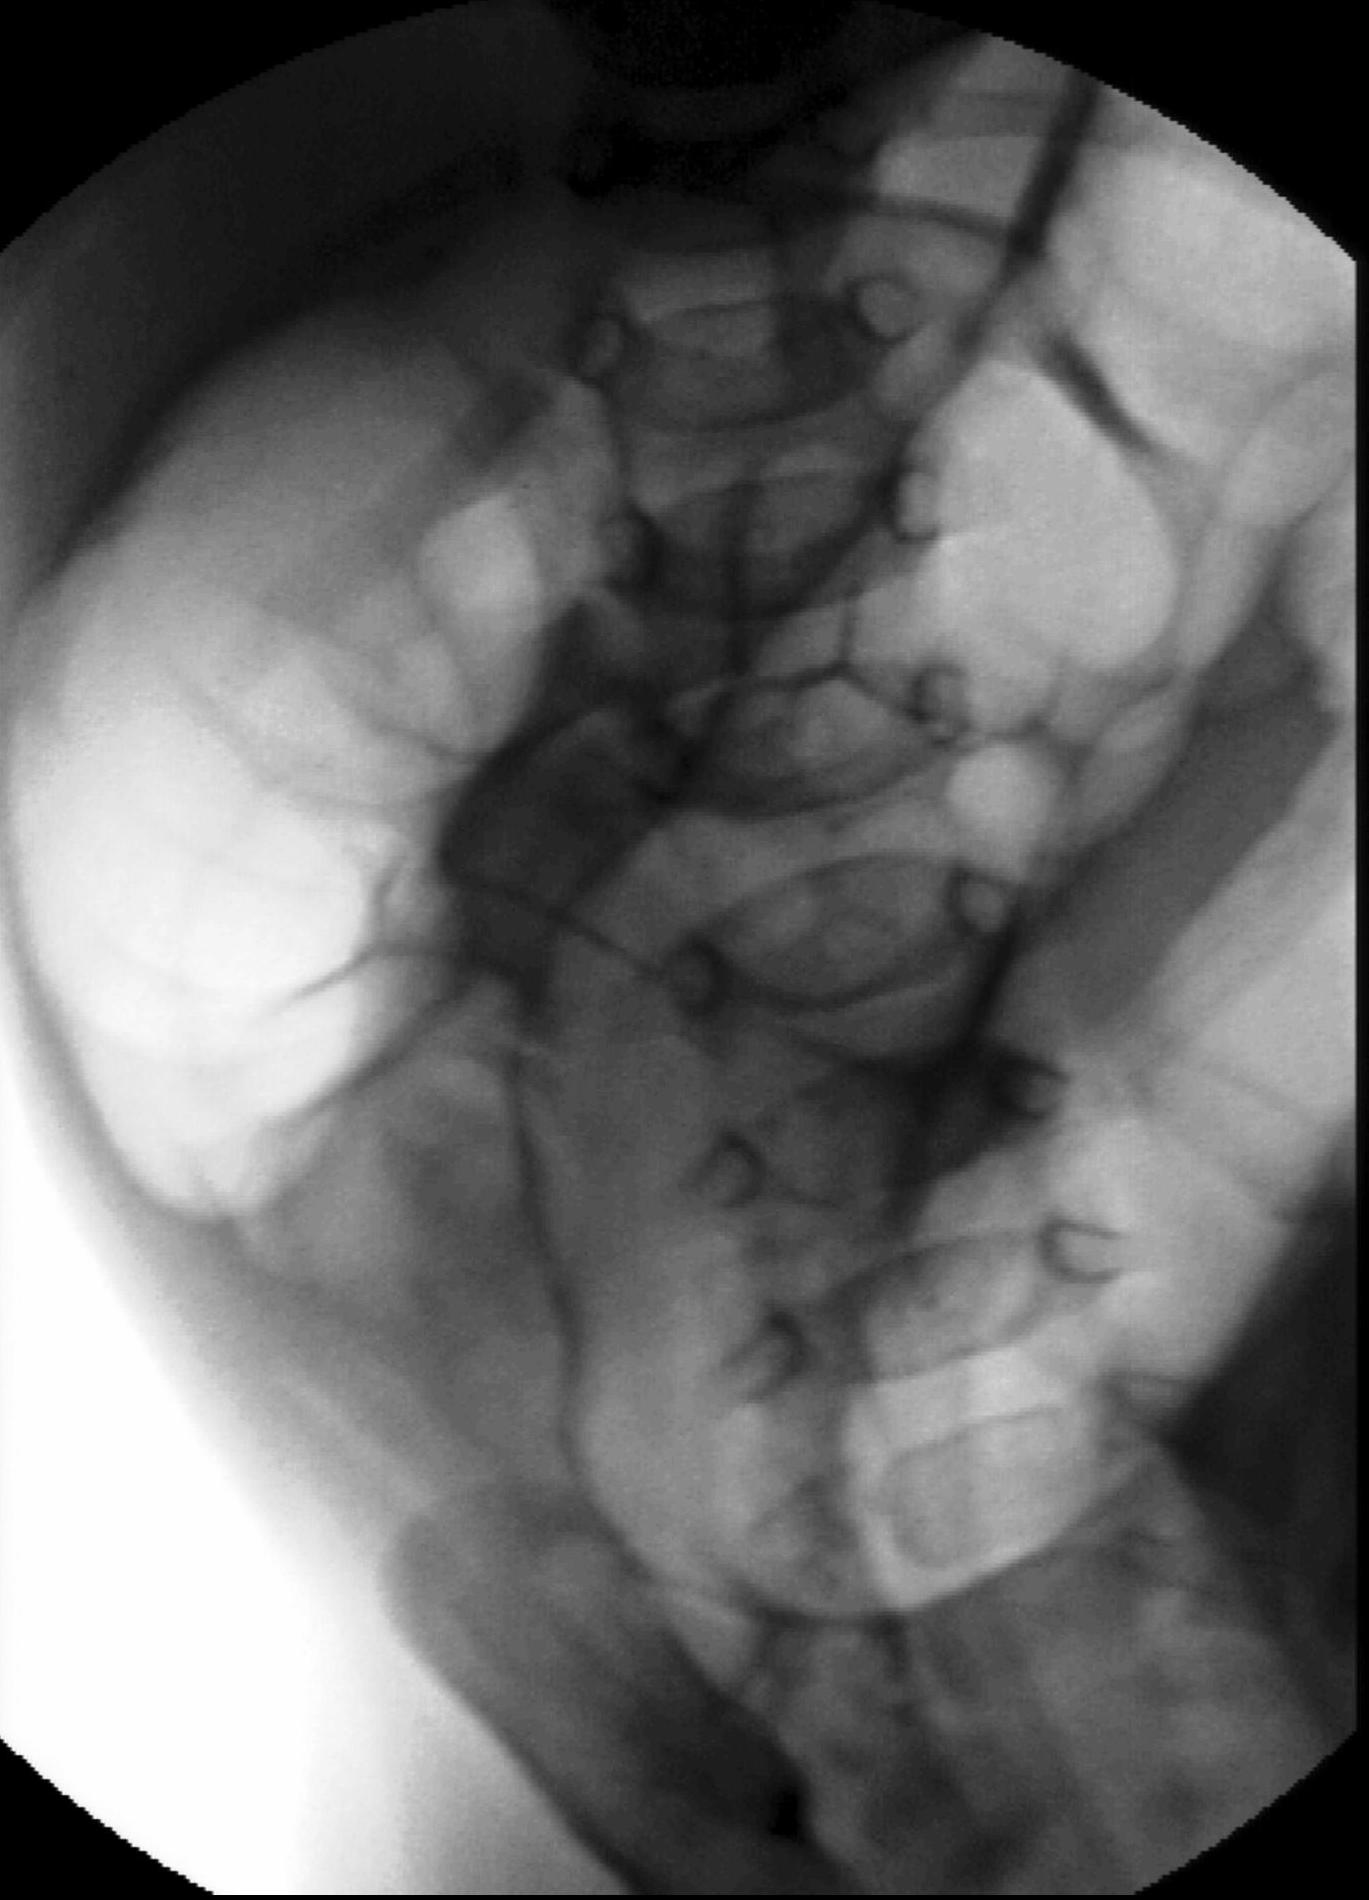

Invagination. A distal intestinal loop invaginating to a proximal intestinal loop can result in a mechanical intestinal obstruction, and cause ischemic damage. It most frequently occurs in infants (3-24 months) with recurring, colic-like complaints, distended intestines, a palpable mass and with frequent vomiting and bloody stool. Invagination requires immediate diagnosis and desinvagination. US exam reveals the invaginated intestines as a “target” sign in axial cross section and looks like a “pseudokidney” in longitudinal cross section. The therapy is hydrostatic or pneumatic desinvagination. Perforation and/or peritonitis are absolute contraindications to these procedures. Hydrostatic desinvagination can be performed under fluoroscopy or with US guidance and is considered successful if air or the contrast material appears in the terminal ileum and the invaginated loop disappears. If these efforts do not succeed, surgical desinvagination is needed.

17. “Target” sign. Invagination. .

18.a-b-c-Desinvagination with air.

18. b. Arrow: invaginated segment.

18. c. Successful desinvagination